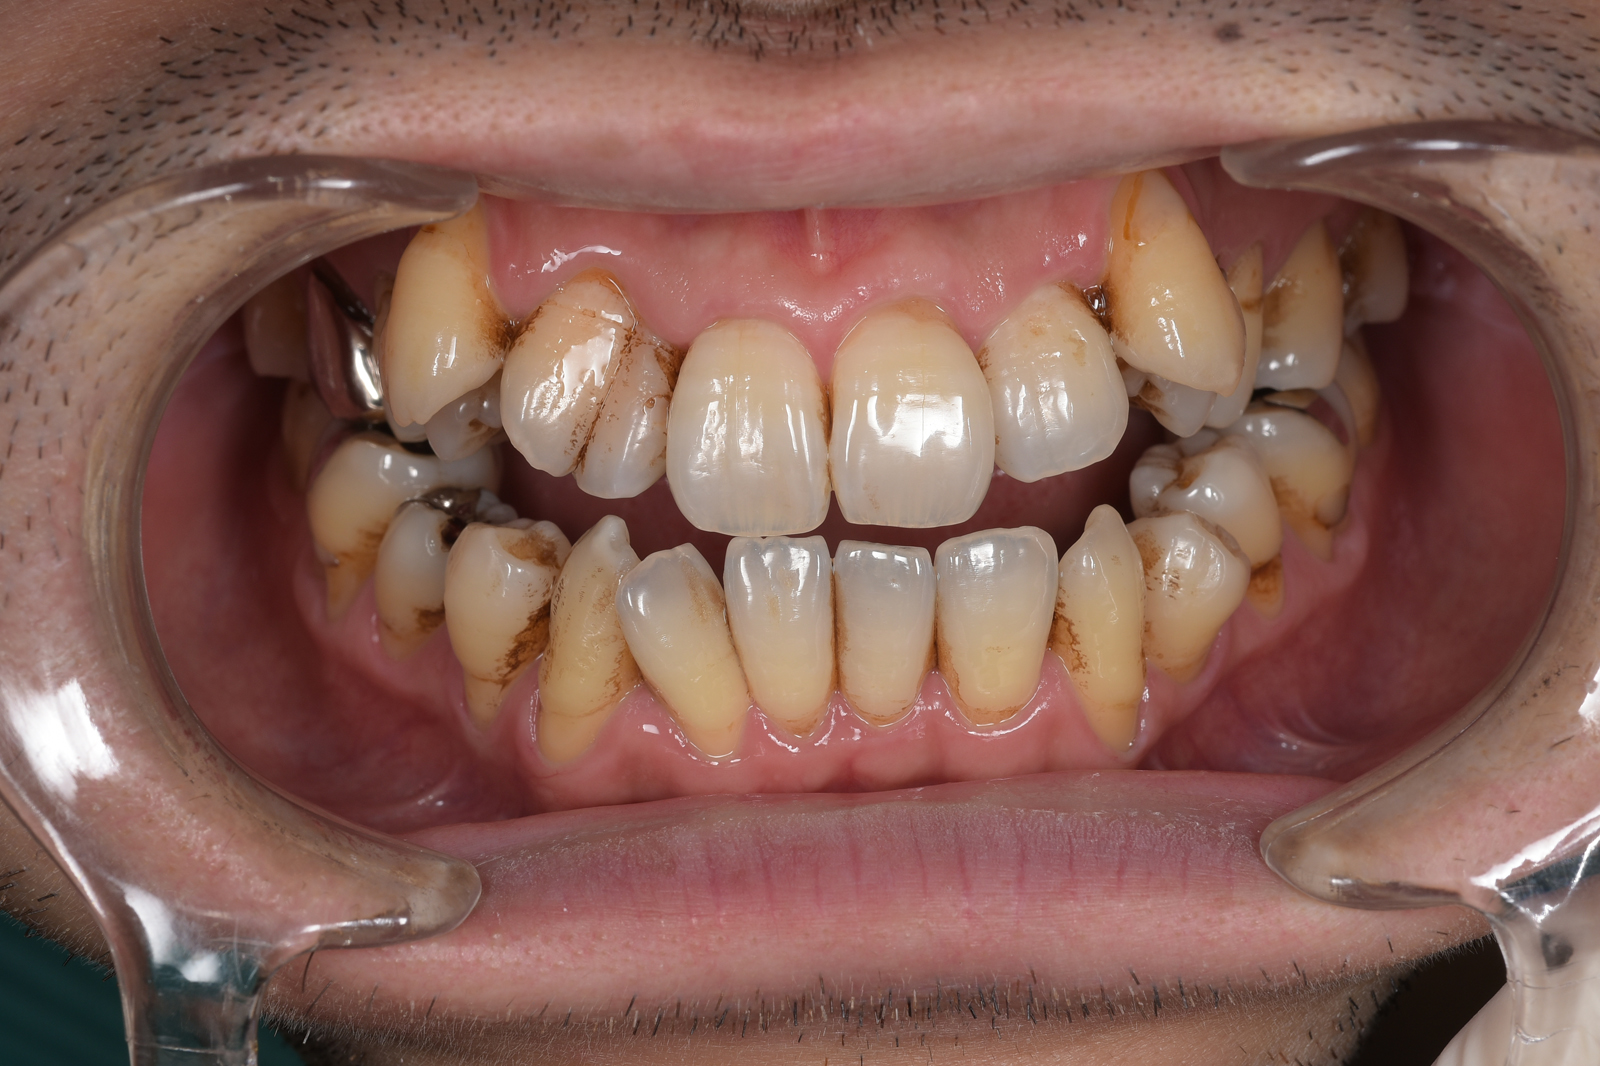

このページをご覧になっている方は、おそらく歯周病に関するお悩みの解決方法をお探しなのだと思います。

きっと、こうしている今も、歯周病が進行してグラグラしている歯があるのではないでしょうか。

皆さんもご存じかと思いますが、歯周病は、歯を支える骨をゆっくり溶かしていき、痛くもないのに歯が抜けていくという恐ろしい病気です。

しかし、心配は無用です。歯周病の原因とそのメカニズムは明らかになっており、早期に治療すれば歯を失わずに済みます。

今からでも遅くはありません。残された歯を守るために、一緒に治療をしていきましょう。